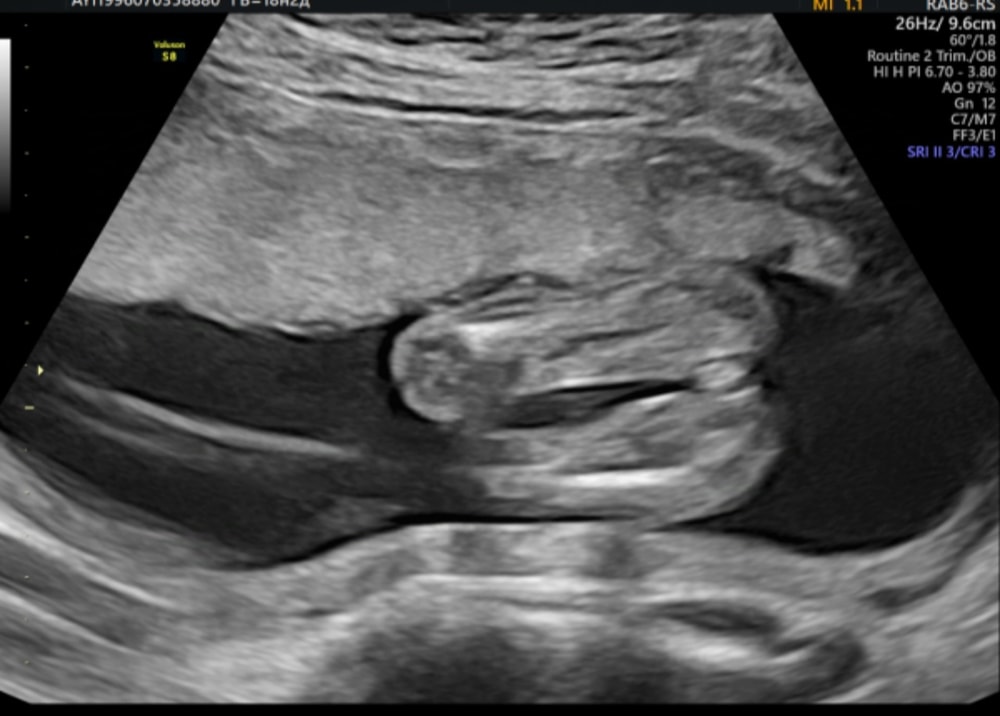

Анализы, скринингиНа каждом УЗИ или скрининге мне все время говорили разный пол,решила пойти по совету знакомой с работы в хорошую по её мнению клинику, где ей не ошиблись ни разу с полом за все её 4 беременности. Так вот, прихожу на узи, минут 30 мне смотрели всё, все органы , кровоток и т.д., в конце УЗИ говорят мальчик и дают вот этот снимок. Я не понимаю, это шутка надо мной что ли или врач уже к вечеру совсем ослеп от усталости😀 я ему сказала, что писюна я не вижу, а вижу так сказать женские органы, но он меня минут 10 пытался убедить , что на снимке яички, а сам хобот ( как выразился сам врач) спрятался наверх 😀

Ну какой мальчик, когда даже для меня , не понимающую ничего в УЗИ это явная девочка ?😀 Походу точно узнаю пол только , когда рожу 😀

У девочек половые губы немного к верху и с такого ракурса это выглядит иначе ). Возможно увидеть только конец половых губ к низу и полоску между ними, если малышка как бы сидит на попе). Скорее всего это правда мальчик )).

Яна, писюн сверху на яичках, а это вид снизу. Честно сказать, с такого ракурса, я тоже не совсем понимаю. Но логично так подумать. Сдайте кровь и не мучайтесь.